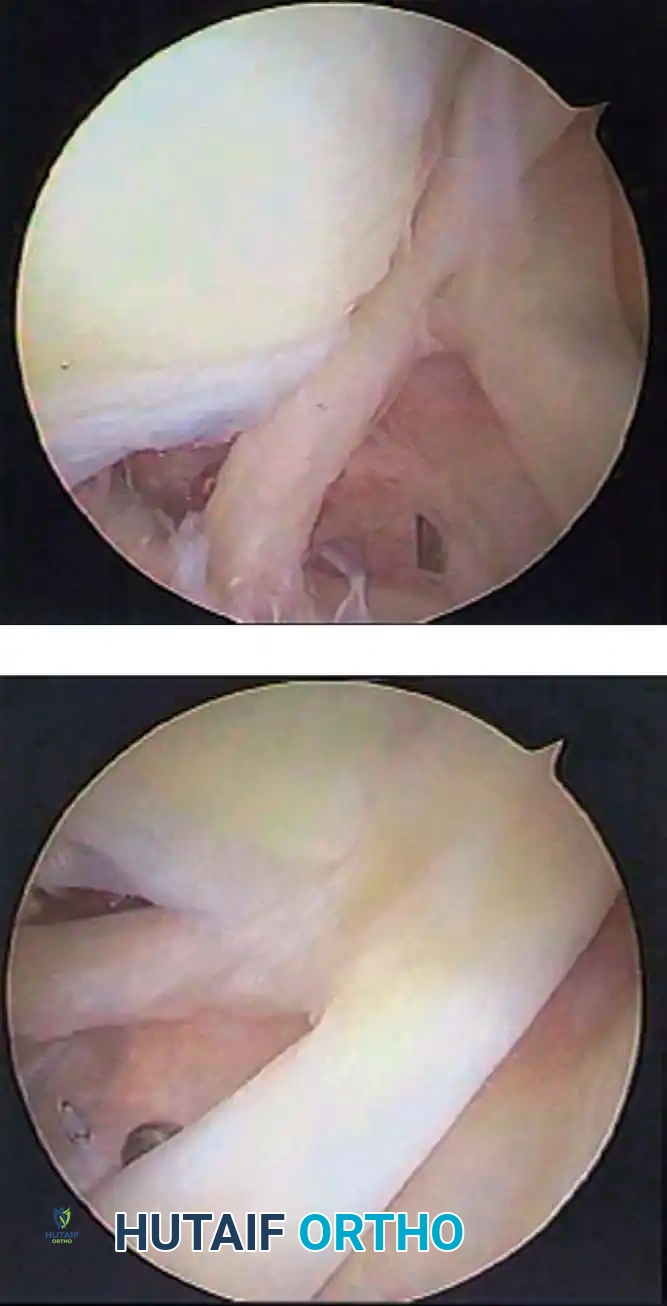

In the overhead throwing athlete, the shoulder is repeatedly placed in extreme abduction, hyperextension, and external rotation (the late cocking phase). This position forces the greater tuberosity and the undersurface of the rotator cuff to impinge against the posterosuperior glenoid rim and labrum. This internal impingement results in fraying of the cuff undersurface and the superior labrum. Repetitive microtrauma leads to anteroinferior ligamentous laxity and a "peel-back" of the posterosuperior capsular complex.

Appropriate surgical intervention relies on a thorough arthroscopic evaluation to decode these complex pathological findings. Diagnostic arthroscopy is also highly indicated for:

Once diagnostic evaluation is complete and hemostasis is secured, the therapeutic phase commences. Whether performing a SLAP repair, a Bankart stabilization, or a rotator cuff repair, the principles of tissue mobilization, anatomical footprint restoration, and secure biomechanical fixation remain paramount.

Modern arthroscopy relies heavily on suture anchors (biocomposite or all-suture constructs) and advanced arthroscopic knot-tying or knotless techniques. The ability to pass sutures through retracted, fibrotic tissue and secure them under appropriate tension without strangulating the microvascular supply is the hallmark of a master arthroscopist.